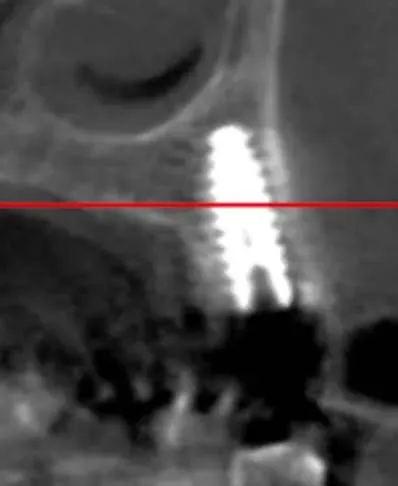

La CBCT dimostra l’anatomia atrofica della zona, con la vicinanza del pavimento del seno mascellare e la significativa perdita di sostanza palatale dovuta all’infezione parodontale.

CBCT di elemento dentario 2.5 affetto da carie e tasca parodontale acuta

CBCT dell’elemento 2.5 con evidenza della vicinanza del seno mascellare e della distruzione del parodonto, soprattutto sul versante palatino.